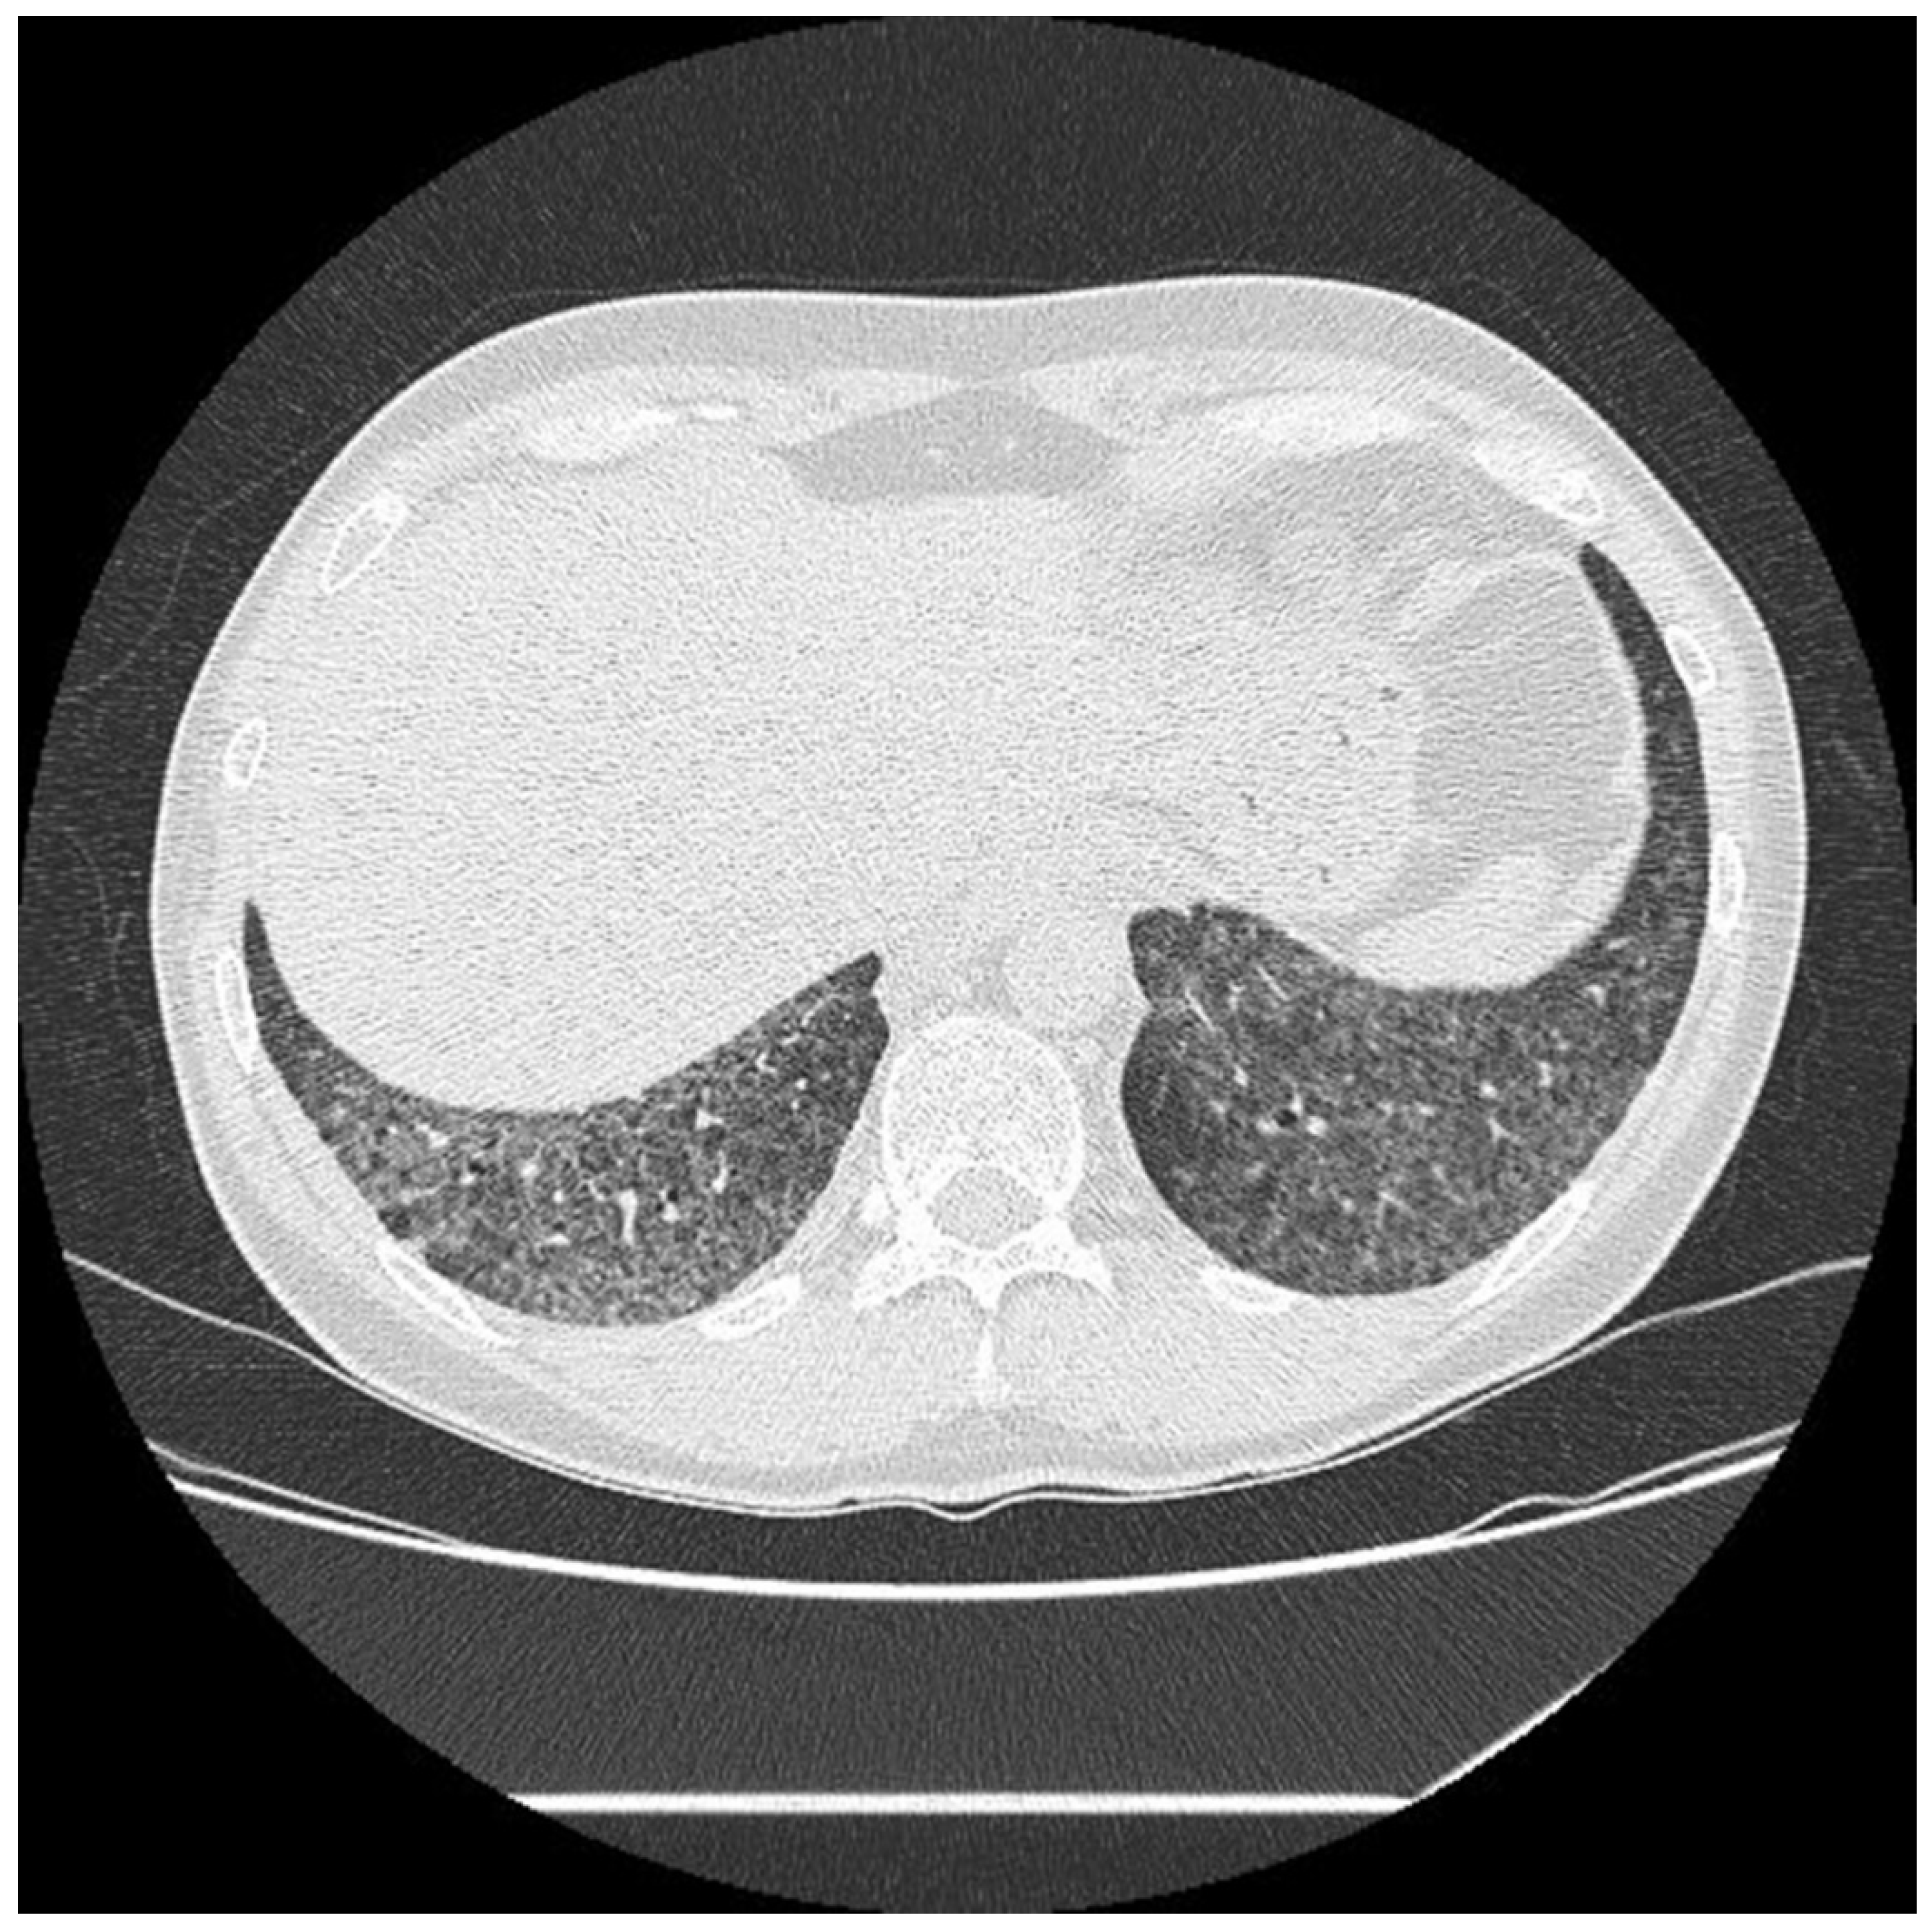

4.1.2. Radiological Testing